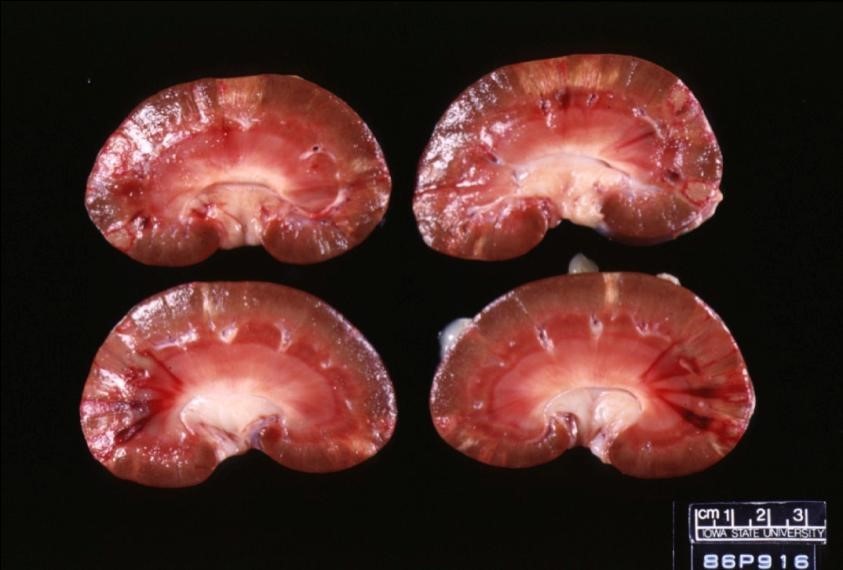

Describe these lesions

Interlobular and interlobar acute infarcts.

Pale tan wedged shaped lesions.

Peripheral haemorrhage

Indented cortical surface

Caused by microthrombi in renal blood supply